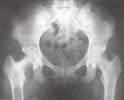

Fig. 1. Radiografía de pelvis que muestra las lesiones

Se trata de una paciente de sexo femenino de 16 años de edad, quien consultó en abril de 1995 al Hospital Universitario de Cartagena por presentar dolor en cadera derecha de tres semanas de evolución, de inicio insidioso y aumento progresivo hasta causar cojera antálgica. Al ingreso se encuentra una paciente con leve obesidad, desarrollo de caracteres sexuales secundarios completo, cojera antálgica, dolor a la pal pación y movilización de cadera derecha con arcos normales de movimiento. La radiografía de ingreso muestra dos lesiones: la primera, en cuello femoral medial, de 2.5 x 2.5 cm. de bordes mal definidos, radiolúcida, con aspecto de vidrio esmerilado y compromiso o erosión extensa de la cortical medial.